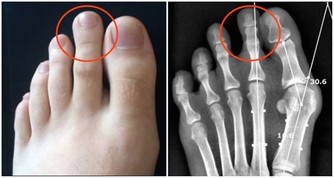

目前中國有1億人左右患有靜脈曲張,靜脈曲張的問題不僅僅是看上去不雅觀,更重要的是,當靜脈曲張累積到深靜脈時,或引起肺栓塞,導致猝死。

所以我們應該對靜脈曲張保持足夠的警惕,及時干預,防止出現深靜脈血栓,增加猝死的風險。因此,今天,我們主要講講靜脈曲張的預防。

以上方法的核心思想就是收縮小腿肌肉,促進血液回流,如果你有其餘的辦法也能達到這種效果,也可以一試。在這裡,主要是給年輕人們提個醒,如果你現在就發現自己有靜脈曲張,一定要加以重視,及時干預,將肺栓塞的可能性降到最低。